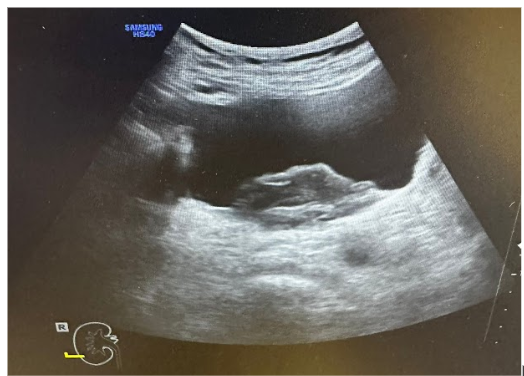

Tras la clínica presentada, se realiza una ecografía clínica abdominal con el fin de orientar el diagnóstico.

Hallazgos ecográficos

Ecografía clínica: Ureterohidronefrosis grado III bilateral con ectasia ureteral bilateral en toda su extensión. Probable proceso neoformativo urinario con dimensiones aproximadas de 5,61 x 2,74 cm.